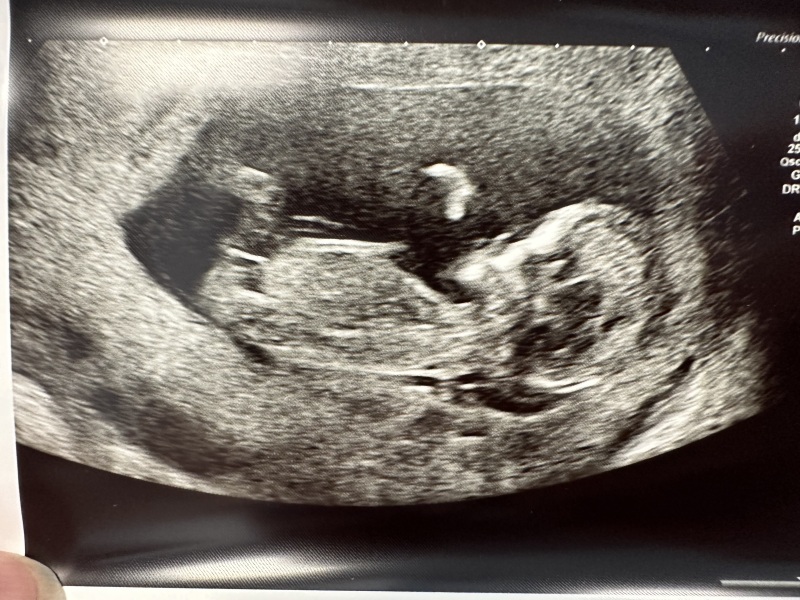

The scan was perfect!! I can’t even believe it!! Baby is measuring 63mm (which seems big for 11+5 😳) and dancing and waving at us 😍 neck fluid measurement really low aswell. Just got to find out more donor details to get full risk factors.

anyone good at nub theory and fancy a guess? We’re not finding out so just for fun 😁😁

@Kelb79 yay even a better picture this time!! ❤️ already so cute!! I think it is a girl, that what was my thought- what a pretty girl she is ☺️

@TT82 i thought girl too! 🩷🩷😍😍